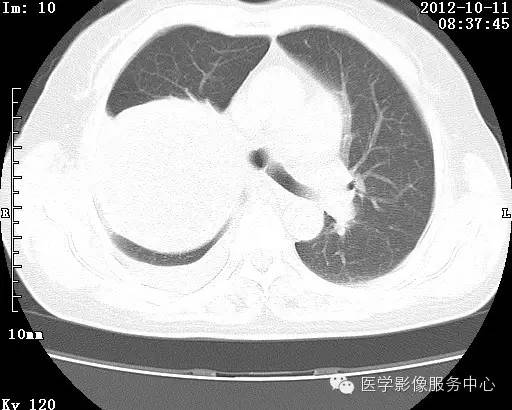

【病例】右肺巨大错构瘤1例CT影像表现

病史:女 65岁咳嗽咳痰 右肺巨大肿块就诊。

理论上肺错构瘤为良性肿瘤,其结节形态、边界、与胸膜关系、与肺门关系、淋巴结肿大及与血管关系均应符合良性肿瘤的特点。

由于不典型错构瘤极易误诊为周围型肺癌和/或结核球,故应与二者鉴别。

结核球患者既往病史中可能有明确的肺结核病史,周围多可见卫 星病灶,增强扫描无强化或仅有包膜强化,此外纵隔 肺门淋巴结多有钙化征象;

周围型肺癌绝大多数边界不光整, 可见短毛刺,钙化不常见,爆米花样钙化更罕见,而 且往往合并有纵隔肺门淋巴结增大增多,患者临床症状较为明显。